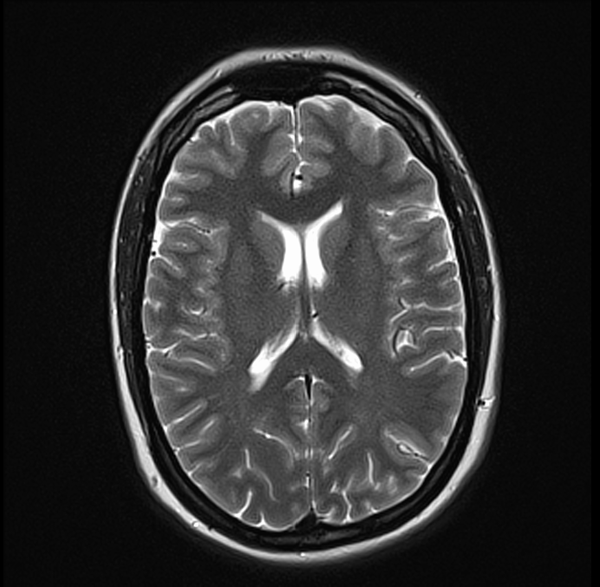

MRI Brain Anatomy 3T 3MM